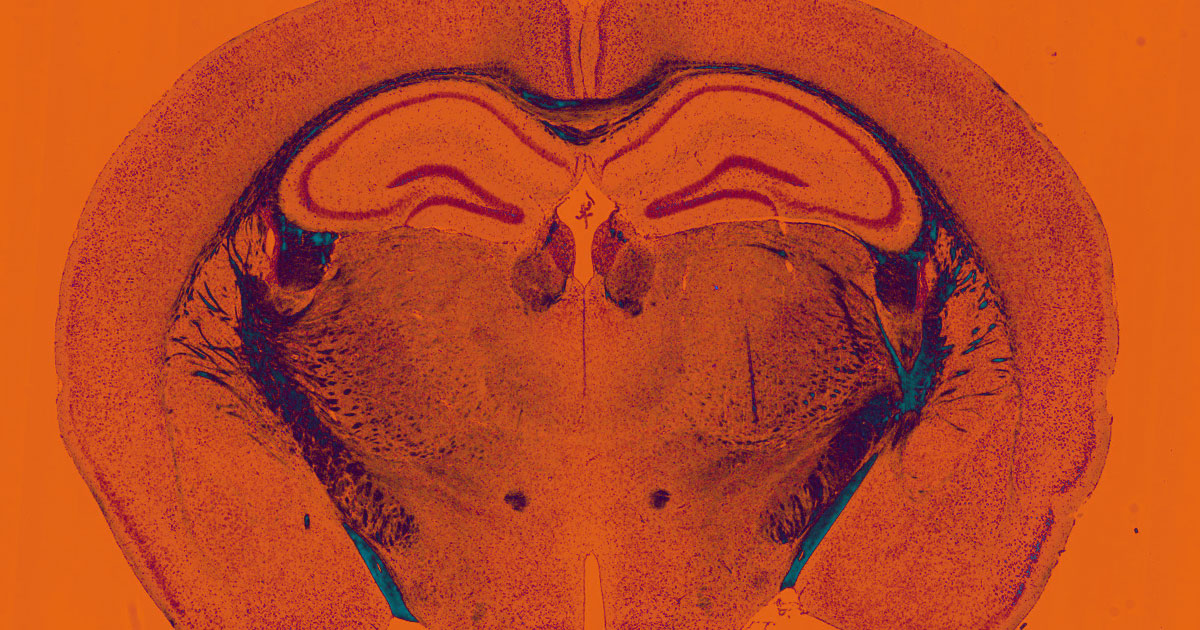

A team of researchers at the RIKEN Center for Biosystems Dynamics Research in Japan have developed a new way to keep brain tissue from animals alive and viable for up to 25 days. So far, scientists have been limited to carrying out experiments with brain tissue for only a couple of days, according to Science Alert.

The researchers expanded on an already-existing technique that involves so-called microfluidic devices — a special and highly precise way to deliver the fluids and nutrients that brain tissue needs to stay alive.

A major hurdle: too much liquid would keep the tissue’s cells from exchanging gases; too little, and it would dry out and die like an old sponge.

To solve the issue, the team developed a new microfluidic device that includes a permeable artificial membrane that allows some — but not all — liquid to pass through, keeping moisture levels just right.